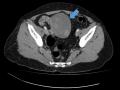

Tag: ultrassonografia transvaginal

Diagnóstico por imagem em ginecologia - Quinto ano medicina